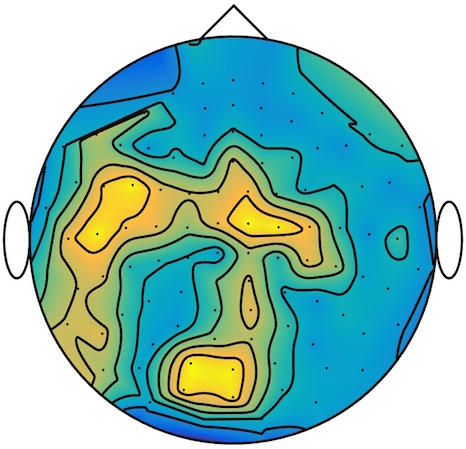

We applied our method to a magnetoencephalography (MEG) dataset. In this setup, brain activity of a subject is recorded (Elekta Neuromag, 306 sensors of which 204 planar gradiometers and 102 magnetometers, sampling frequency 1000Hz) while the subject reacted to the presentation of a target stimulus by pressing either the left or the right button.

Data is preprocessed applying signal space separation correction, interpolation of noisy sensors, and realignment of data into a subject-specific head position (MaxFilter, Elekta Neuromag). The signal was then filtered (low pass 40HZ), and artifacts such as blinks and heartbeats removed thanks to Signal-Space Projection using the Brainstorm software222http://neuroimage.usc.edu/brainstorm. The samples we used for our barycenter computations are an average of the norm of the two gradiometers for each channel from stimulation onto 50ms and the classes were left or right button.

| Class 1 | Class 2 | ||||||

|

|

|

|

|

|

|

|

| Sample 1 | Sample 2 | Sample 3 | Mean | Sample 1 | Sample 2 | Sample 3 | Mean |

|

|

|

|

|

|

|

|

This results in two classes of recordings, one for each pressed button. We aim at computing a representative activity map for each class using Wasserstein barycenters. For each class we have recordings each having samples located on the vertices of an hexahedral mesh of a hemisphere (corresponding to a MEG recording helmet). These recorded values are positive by construction, and we rescale them linearly to impose . Figure 6, top row, shows some samples from this dataset, displayed using interpolated colors as well as iso-level curves. The black dots represent the position of the electrodes on the half-sphere of the helmet, flattened on a 2-D disk.

We computed TV-regularized barycenters independently for each class by solving (16) with the TV regularization using the projected gradient descent method (22). We used a squared Euclidean metric (24) on the flattened hemisphere. Since the data is defined on an irregular graph, instead of (23), we use a graph-based discrete gradient. We denote the graph which connects neighboring electrodes. The gradient operator on the graph is

The total variation on this graph is then obtained by using , the norm, i.e. we use in (23).

Figure 6 compares the naive barycenters (i.e. the usual mean), barycenters obtained without regularization (i.e. ) and barycenters computed with an increasing regularization strength . The input histograms being very noisy, the use of regularization is important to make the area of significant activity emerge from the noise. The use of a TV regularization helps to keep a sharp transition between active and non-active regions.